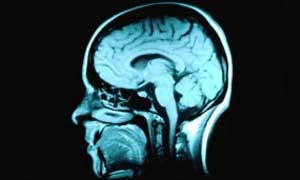

Pornografia pode estar associada a redução daatividade cerebral (Foto: Corbis Royalty Free)

Os voluntários também foram submetidos a um exame de ressonância magnética do cérebro para medir seu volume e observar como ele reagia às imagens pornográficas.